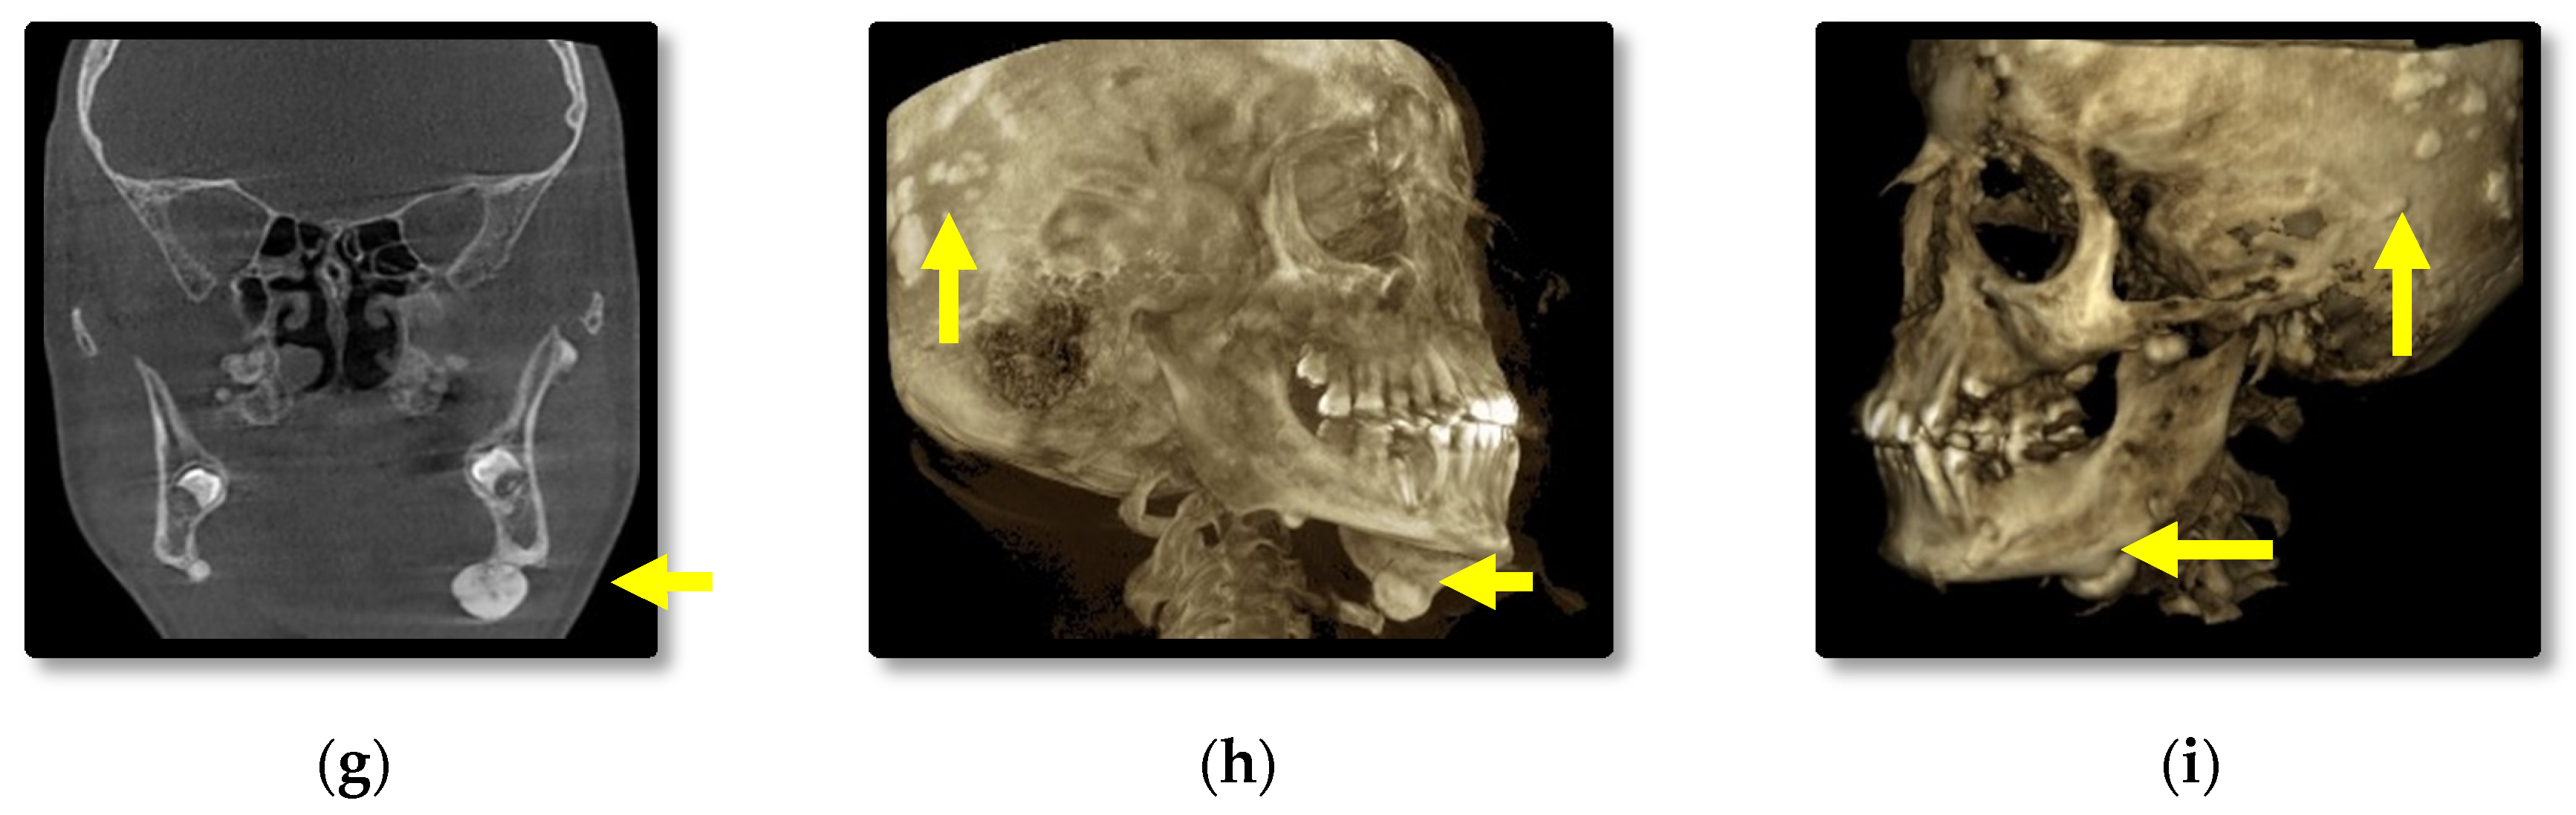

3.1. Radiographic Assessment

4.2. Osteomas